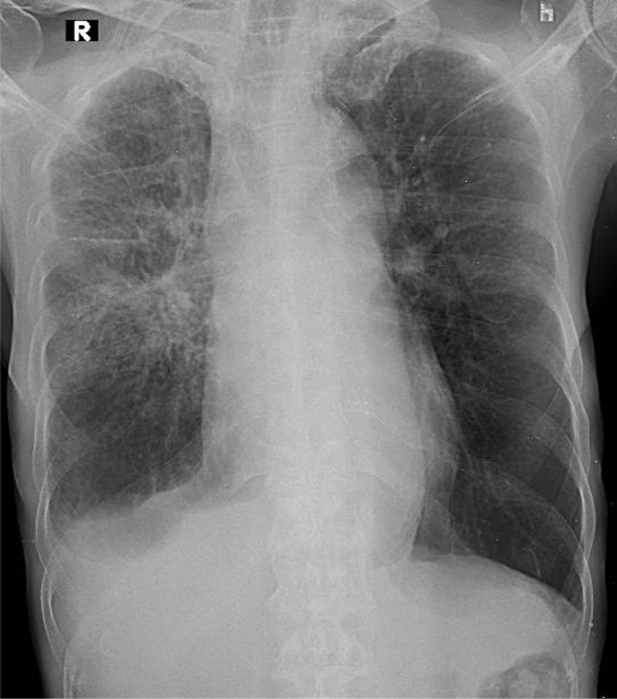

1-Thâm nhiễm mô kẻ rải rác phổi (P) => Viêm phổi 2-Khí phế thũng rải rác hai phổi 3-Tràn dịch màng phổi (P)